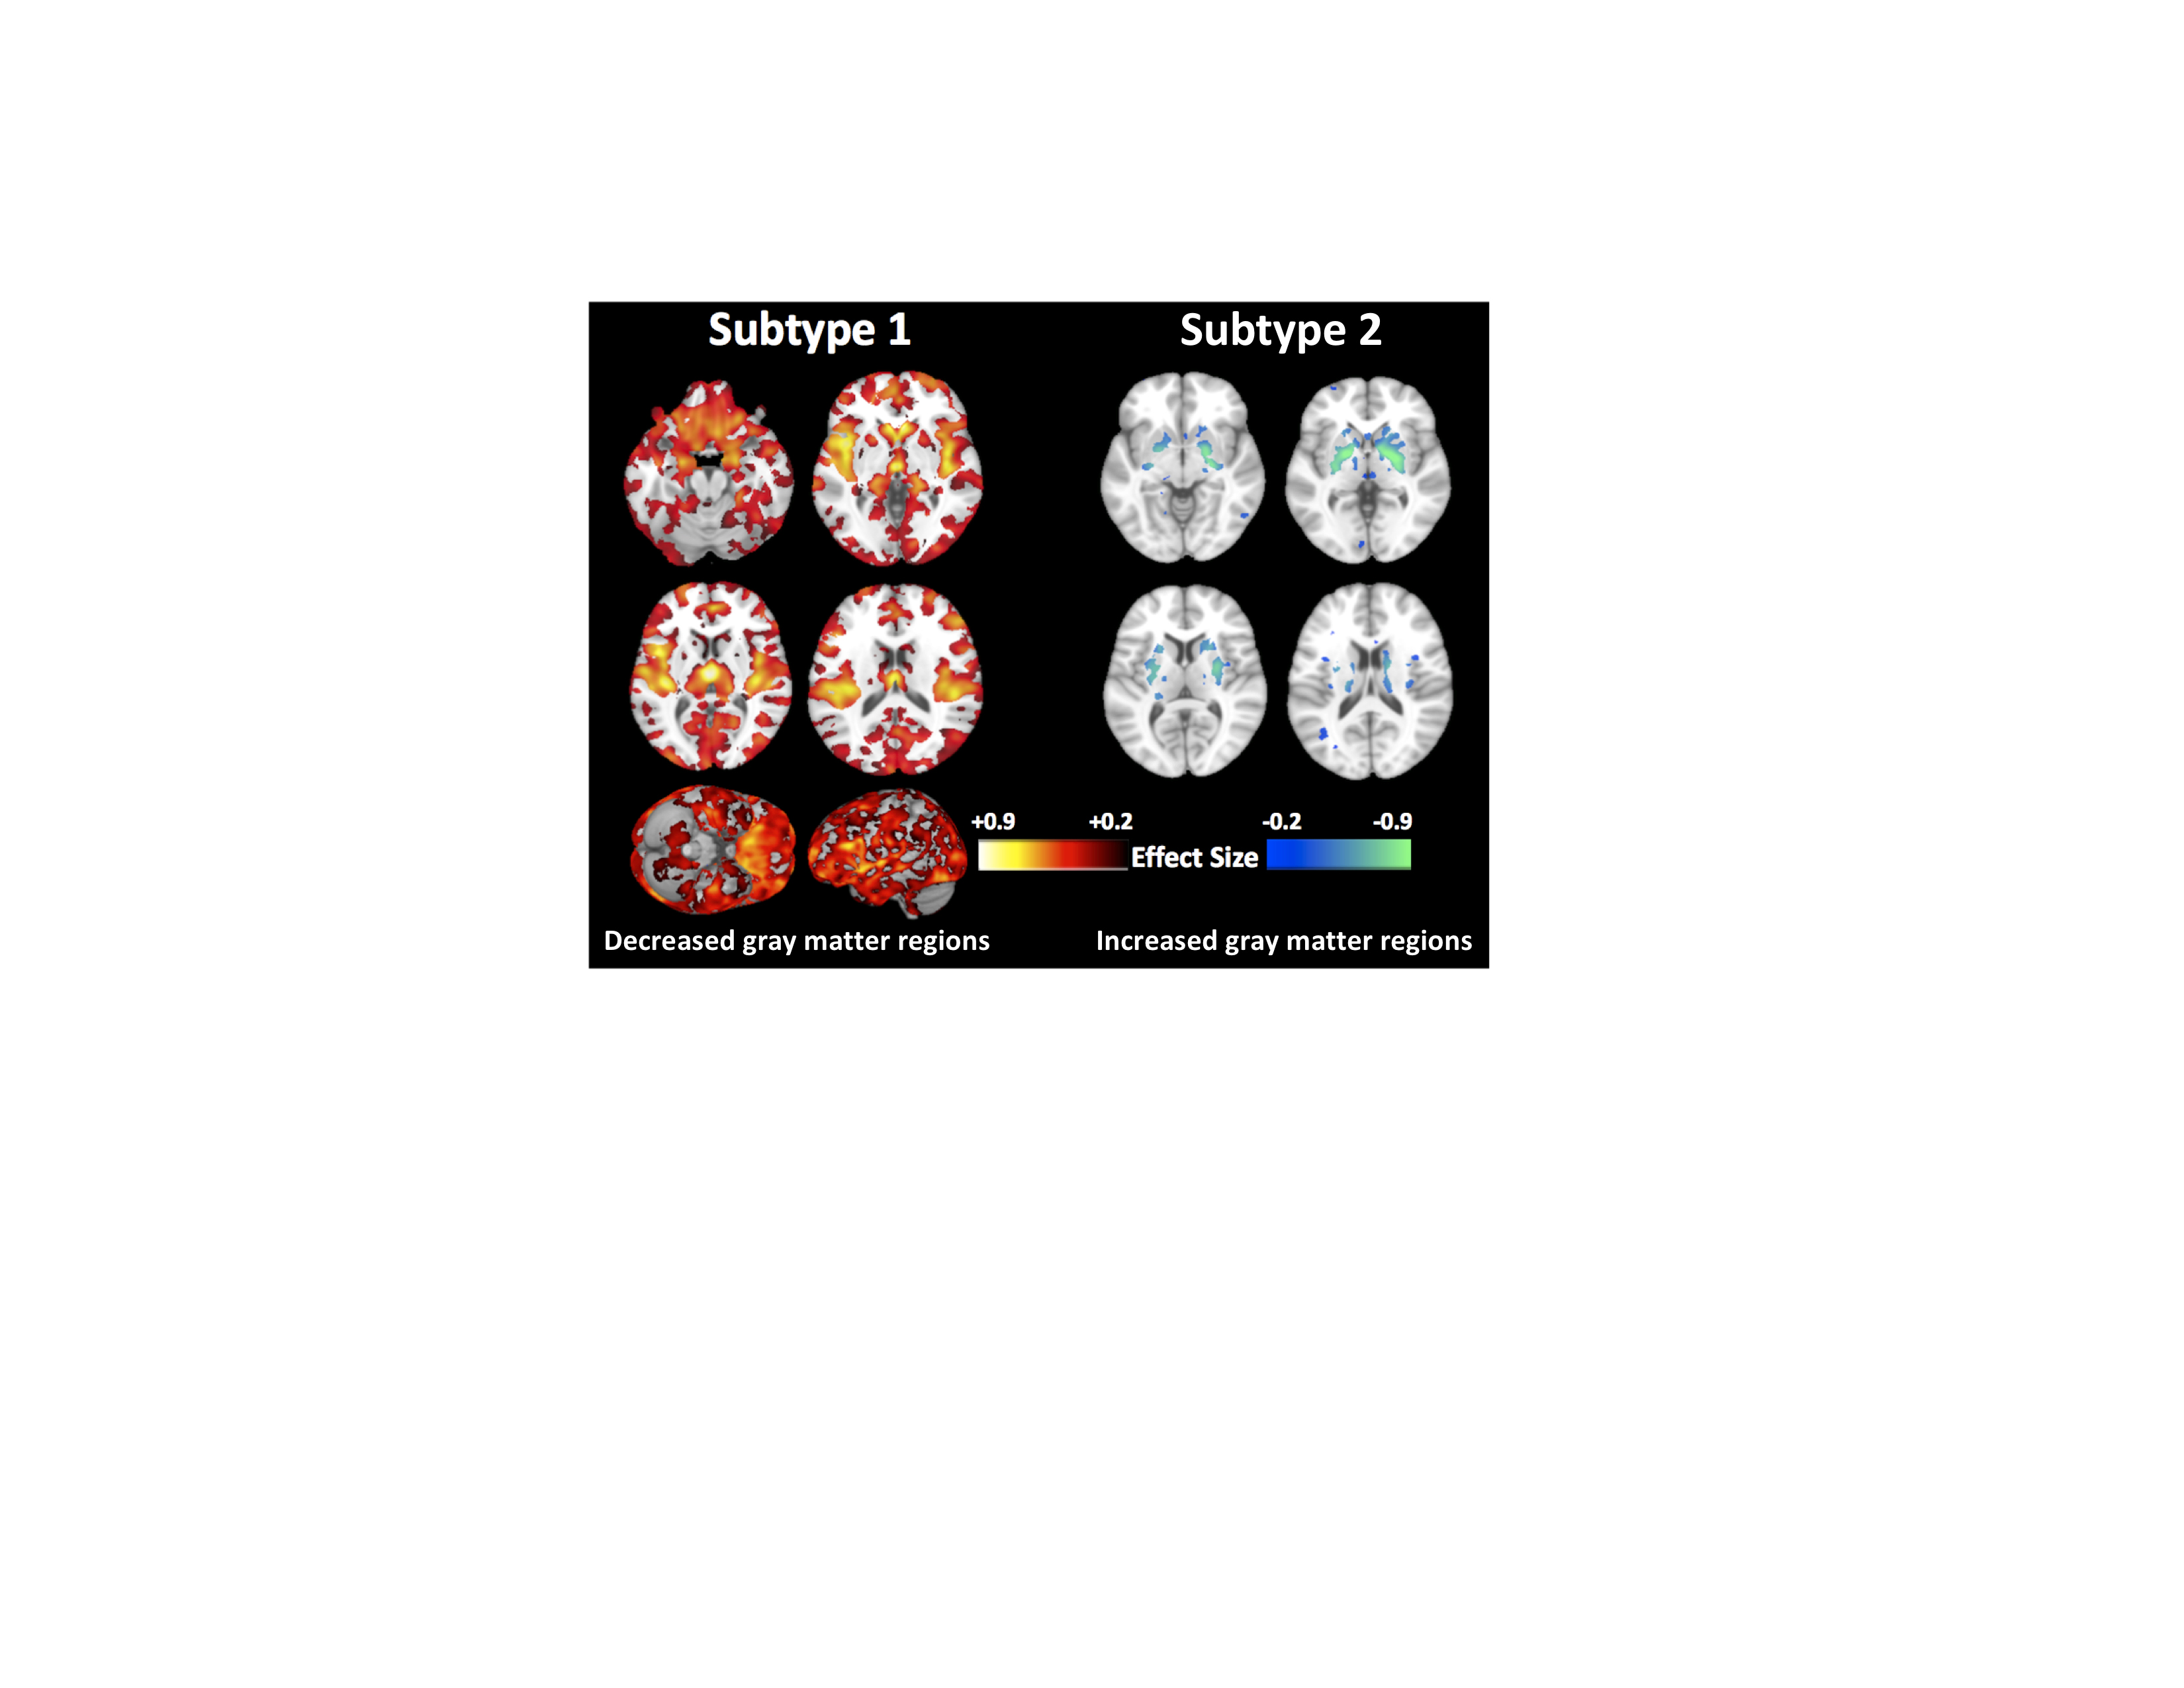

• CIBERSAM

Descubren un segundo tipo de esquizofrenia que puede darse en cuatro de cada diez pacientes

30/04/2020